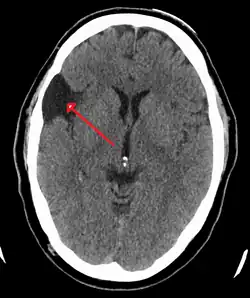

| A CT scan of an arachnoid cyst | |

The diagnostic process typically begins with a medical history workup followed by a medical examination by a physician. Imaging tests, such as CT scans and MRIs, help provide a clearer picture. The physician typically looks for fluid (or other bodily substance) filled sacs to appear in the scans, as is shown in the CT scan of a colloid cyst. A primary health care provider will refer an individual to a neurologist or neurosurgeon for further examination. Other diagnostic methods include radiological examinations and macroscopic examinations. After a diagnosis has been made, immunohistochemistry may be used to differentiate between epithelial cysts and arachnoid cysts.[2] These examinations are useful to get a general idea of possible treatment options, but can be unsatisfactory to diagnose CNS cysts.[3][5] Professionals still do not fully understand how cysts form; however, analyzing the walls of different cyst types, using electron microscopes and light microscopes, has proven to be the best diagnostic tool. This has led to more accurate cyst classification and correct course of action for treatments that are cyst specific. In the past, before imaging scans or tests were available, medical professionals could only diagnose cysts via exploratory surgery.[2]